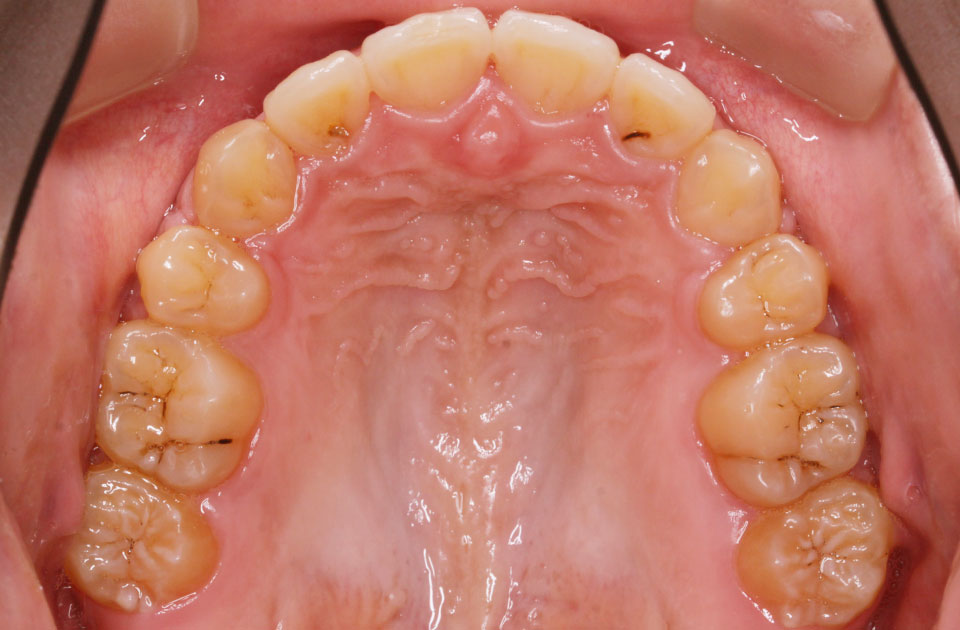

矯正前 上顎